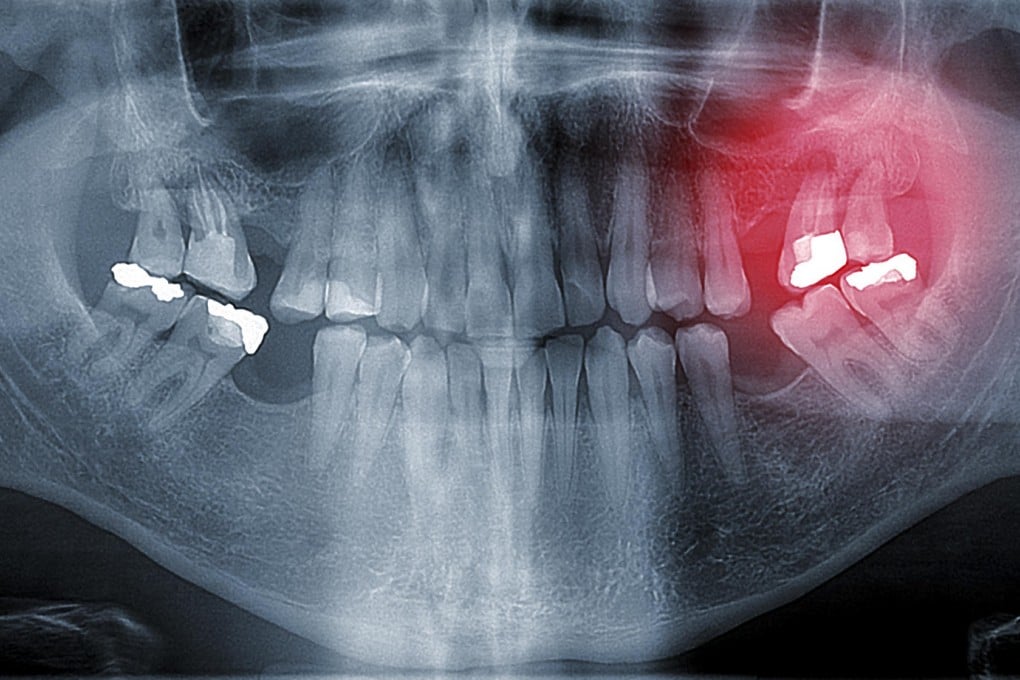

Mercury is a poison that's more toxic than arsenic. So why is it still an ingredient in dental fillings? The campaign against amalgam fillings - made with a mixture of mercury and other metals, and used for more than 150 years - got a boost in October when an international treaty to control the use of the toxic metal, the United Nations Minamata Convention on Mercury, was signed into action.

Amalgam, or silver, fillings have been hotly debated since the 1970s. It was enough to persuade Sweden to ban them in 1997 after determining that 250,000 Swedes had immune disorders and other ailments as a direct result of the mercury in their fillings.

While scientists agree that dental amalgam fillings slowly release mercury vapour into the mouth, the amount of mercury released and the question of whether this exposure presents a significant health risk remain controversial.